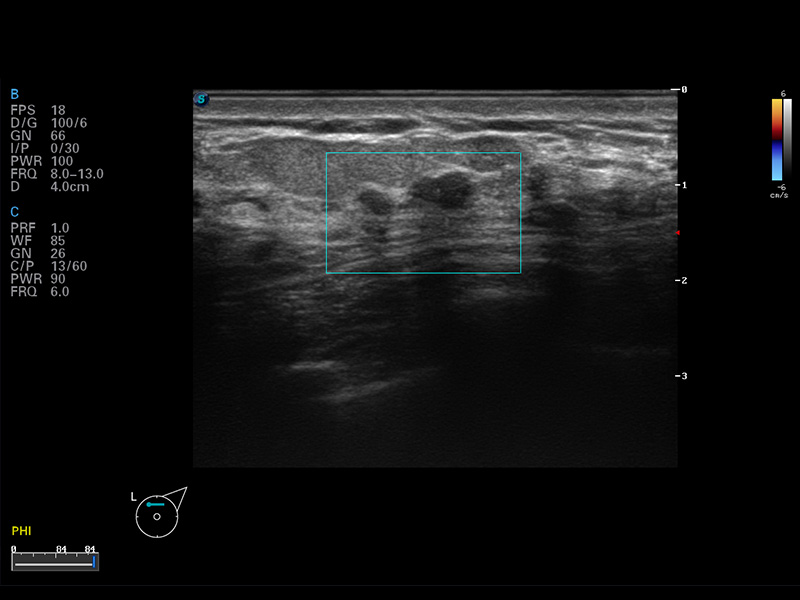

S8 EXP便携式彩色多普勒超声诊断仪是银河优越会研发的高端全身应用型便携彩超。高通道的VIS平台融合可视化(Visual)、智能化(Intelligent)和人性化(Smart)的特点,配以银河优越会自主研发生产的探头大家族,使您能够快速、准确的获得病人信息,提高工作效率的同时减轻疲劳。

μ-Scan微米成像

空间复合成像